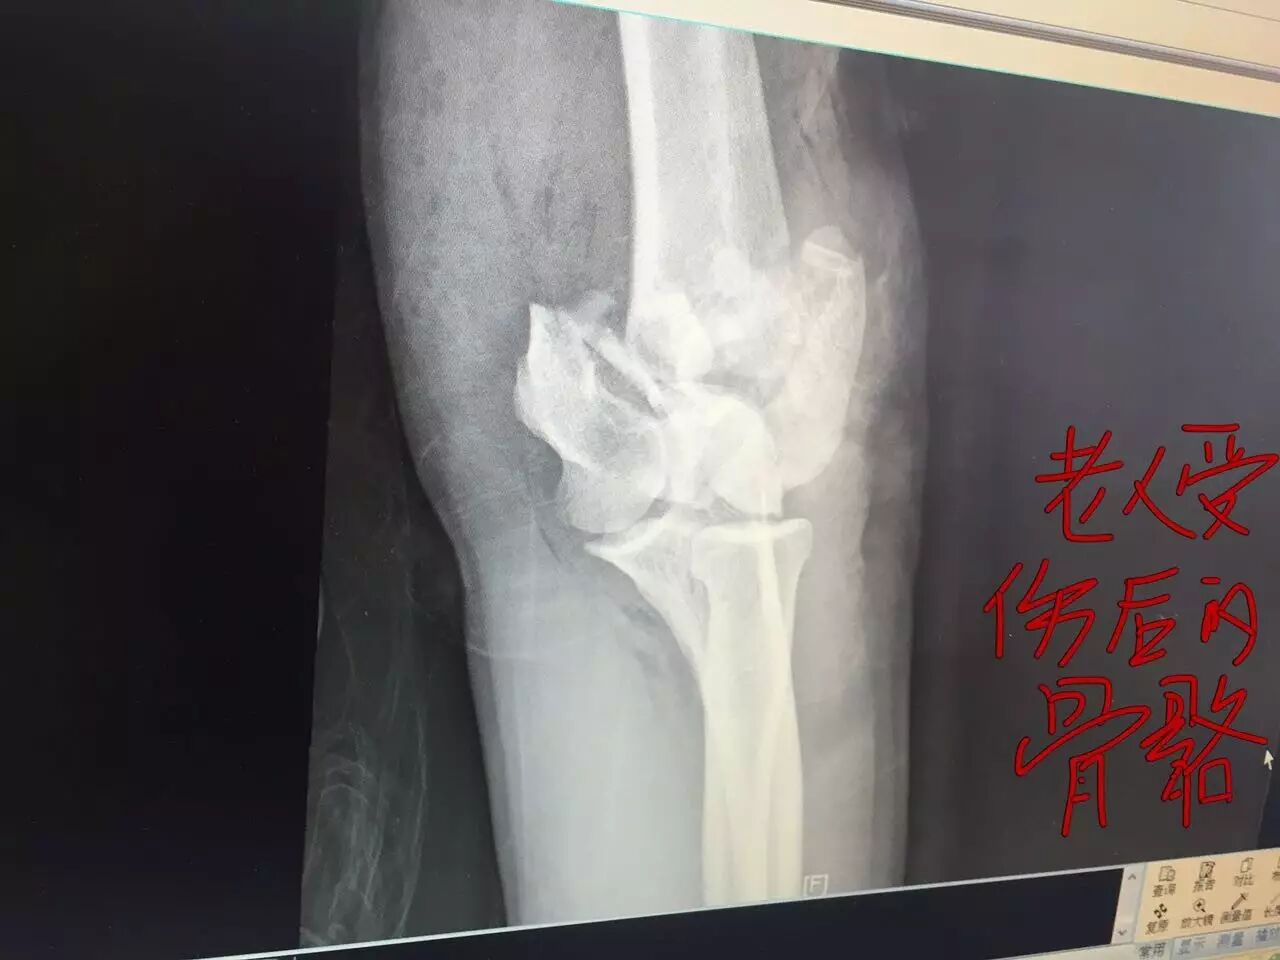

老鄉(xiāng)給記者看,上午醫(yī)生給的檢查結(jié)果,說(shuō)這兩天還要做很多檢查,還要?jiǎng)邮中g(shù)。

老人受傷圖

↓↓↓↓↓↓

(前方高能… 謹(jǐn)慎…)

記者在急診科的檢查結(jié)果上看到,初步診斷老人面部損傷、下肢損傷、骼骨骨折、肱骨骨折、上肢皮膚裂傷。于是記者找到管床的醫(yī)生,他告訴記者,最嚴(yán)重的是左手,里面的骨頭已經(jīng)碎了,等其他傷口消炎后一周左右要做“骨骼切開復(fù)位內(nèi)固定”手術(shù),拼接骨頭,安裝鋼板,要休養(yǎng)三個(gè)月到半年才能工作。醫(yī)生說(shuō),擔(dān)心病人頭部有受傷,還要做腦部CT平掃。